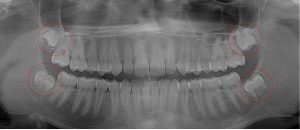

This 19 year old patient has all four 3rd molars present (circled). The roots are +90% formed. Both lower 3rd molars are impacted against the 2nd molars with no chance of further eruption and a +60% probability of decaying before age 30. The patient presented with pain and infection around both lower 3rd molars, requiring immediate extraction